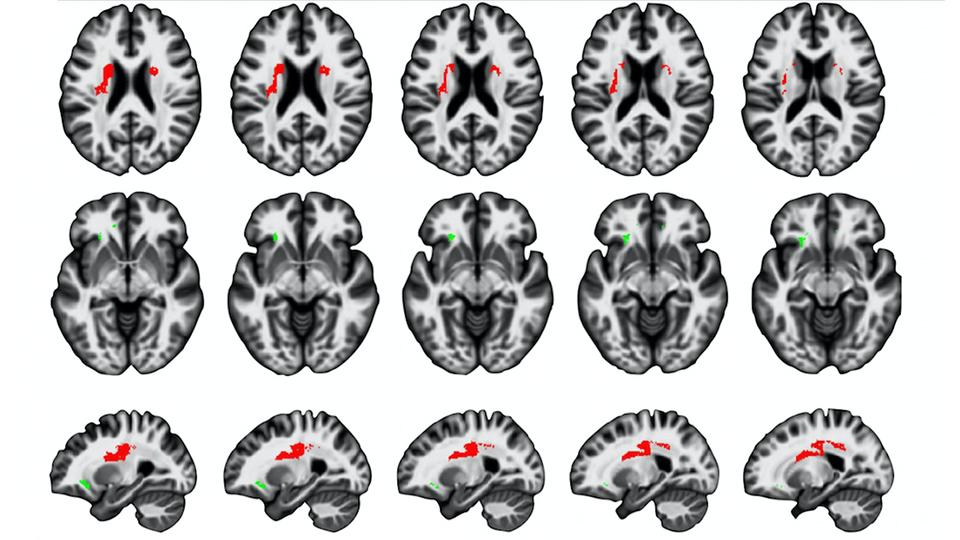

Cappelletti, Marinella; Chamberlain, Rebecca; Freemana, Elliot D.; Kanai, Ryota; Butterworth, Brian; Price, Cathy J. and Rees, Geraint. 2014. Commonalities for Numerical and Continuous Quantity Skills at Temporo-parietal Junction. Journal of Cognitive Neuroscience, 26(5), pp. 986-999. ISSN 0898-929X

Cappelletti, Marinella; Gessaroli, Erica; Hithersay, Rosalyn; Mitolo, Micaela; Didino, Daniele; Kanai, Ryota; Cohen Kadosh, Roi and Walsh, Vincent. 2013. Transfer of Cognitive Training across Magnitude Dimensions Achieved with Concurrent Brain Stimulation of the Parietal Lobe. Journal of Neuroscience, 33(37), 14899 -14907. ISSN 0270-6474

Cappelletti, Marinella; Ling Lee, Hwee; Freemana, Elliot D. and Price, Cathy J.. 2010. The Role of Right and Left Parietal Lobes in the Conceptual Processing of Numbers. Journal of Cognitive Neuroscience, 22(2), pp. 331-346. ISSN 0898-929X